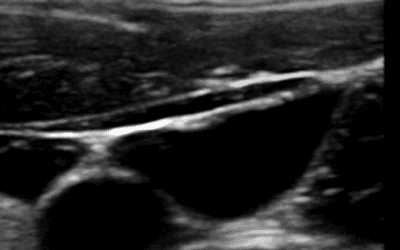

¿Cómo diferenciar el vaso arterial del vaso venoso ecográficamente en el paciente neonatal?